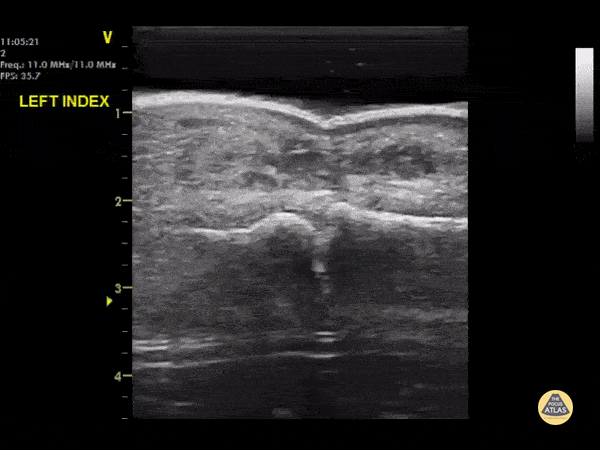

A waterbath-augmented soft-tissue ultrasound of the LEFT index finger was used to diagnose an abscess at the level of the DIPJ Note a hypoechoic collection in the soft tissues sitting on top of the flexor tendon sheath Learning point : Immerse the hand in a waterbath to increase image quality for distal extremities - the water allows improved sound wave transmission Dr Cian McDermott, Mater University Hospital, Dublin, Ireland